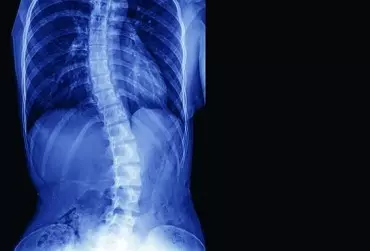

Leczenie skolioz, kifoz, lordoz z uwzględnieniem m.in. zasad metody FED

Ośrodek Specjalistycznej Fizjoterapii „BIO” Mariusz Czarnecki jako trzeci ośrodek w Polsce wprowadził w 2011 r. metodę FED. Ma on duże doświadczenie w bez- operacyjnym leczeniu skolioz, kifoz i lordoz. W niniejszym materiale przedstawiono wybrane przypadki i wyniki leczenia.